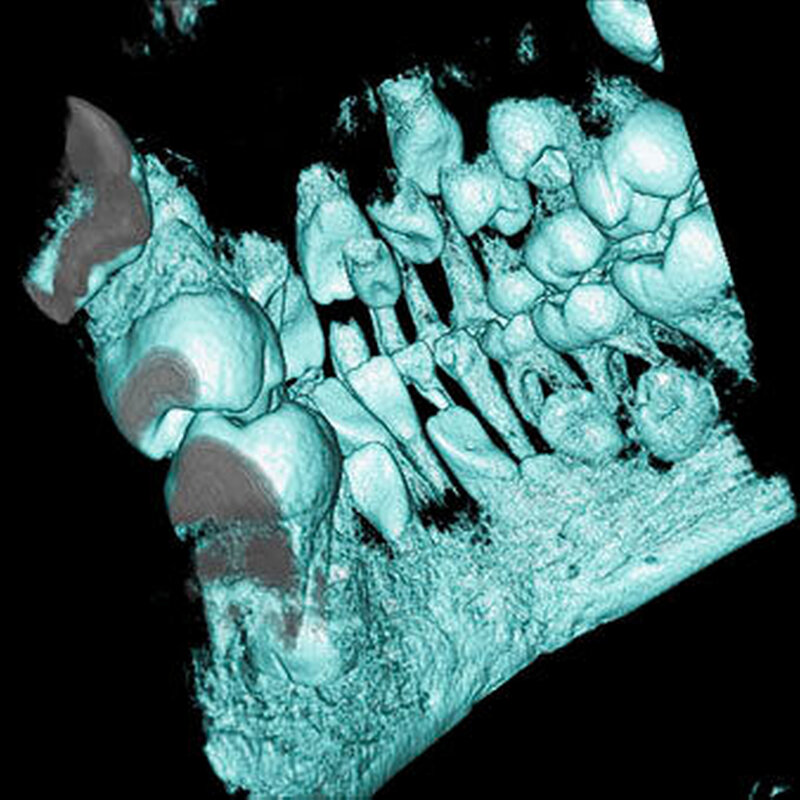

Überzählige Zähne können einzeln oder multipel auftreten [von Arx, 1990; Rajab Hamdan, 2002; Fernández Montenegro et al., 2006; Liu et al., 2007; Gündüz et al., 2008; Ferrés-Padró et al., 2009; Hyun et al., 2009]. Einzelne überzählige Zähne treten in 65,8 bis 80,5 Prozent, doppelte in 14,5 bis 27,7 Prozent und multiple in 0,6 bis 8 Prozent der Fälle auf [Rajab Hamdan, 2002; Fernández Montenegro et al., 2006; Liu et al., 2007; Ferrés-Padró et al., 2009; Hyun et al, 2009; Mossaz et al., 2014]. Einzelne oder doppelte überzählige Zähne finden sich typischerweise in der Oberkieferfront [Rajab Hamdan, 2002; Fernández Montenegroet al., 2006; Mossaz et al., 2014]. Multiple überzählige Zähne werden vor allem im Prämolarenbereich des Unterkiefers gefunden [Abbildung 4; YUSOF 1990, Ferrés-Padróet al., 2009; Wang Fan, 2011]. Multiple überzählige Zähne sind zudem oft mit anderen Erkrankungen oder Syndromen assoziiert, dazu gehören Lippen-Kiefer-Gaumenspalten, die cleidokraniale Dysplasie oder auch das Gardner-Syndrom. Bei Patienten mit einer Lippen-Kiefer-Gaumenspalte wird vermutet, dass sich die überzähligen Zähne aus der Fragmentierung der dentalen Lamina bei der Spaltbildung ergeben [Garvey et al., 1999; Wang Fan, 2011].

Überzählige Zähne werden nach ihrer Lage im Zahnbogen und auch aufgrund ihrer Morphologie eingeteilt. Basierend auf der Lage unterscheidet man bei überzähligen Zähnen zwischen Mesiodens (Oberkiefer median), zwischen den zentralen Inzisiven (Abbildungen 5 und 6), einem zusätzlichen Schneidezahn (zentral oder lateral), Eckzahn, Prämolar (Abbildung 7), Paramolar und Distomolar (Abbildungen 8). Mesiodentes werden am häufigsten dia- gnostiziert, wobei Prozentsätze zwischen 38,8 Prozent bis 86,3 Prozent der überzähligen Zähne in der Literatur zu finden sind [Salcido-García et al., 2004/38,8 Prozent, Fernández Montenegro et al., 2006 /46.9 Prozent; Mossaz et al., 2014/48.5 Prozent; Ferrés-Padró et al., 2009/53.2 Prozent; Schmuckli et al., 2010/75 Prozent; Rajab Hamdan 2002/83.2 Prozent; Liu et al., 2007/86.3 Prozent]. Überzählige Prämolaren und seitliche Schneidezähne sind die zweithäufigste Gruppe der überzähligen Zähne. Überzählige Eckzähne, Paramolaren und Distomolaren dagegen gelten als eher selten [Rajab Hamdan, 2002; Salcido- García et al., 2004; Liu et al., 2007; Ferrés-Padró et al., 2009; Schmuckli et al., 2010; Mossaz et al., 2014]. Einzig eine Spanische Gruppe [Fernández Montenegro et. al., 2006] berichtete, dass Paramolaren und Distomolaren insgesamt relativ häufig seien (18 Prozent, beziehungsweise 5,6 Prozent). Überzählige Zähne kommen im Ober- und Unterkiefer vor, wobei sich überzählige Schneidezähne in der Regel im Oberkiefer, überzählige Prämolaren sich dagegen eher im Unterkiefer befinden [Fernández Montenegro et al., 2006; Ferrés-Padró et al., 2009; Mossaz et al., 2014]. Überzählige Molaren wiederum treten normalerweise im Oberkiefer auf [Cassetta et al., 2014; Kaya et al., 2014].

Überzählige Zähne können sich in der Richtung des normalen Durchbruchs entwickeln oder sie können inkliniert, horizontal oder in einer umgekehrten Position (invers) liegen. Ungefähr ein Drittel bis die Hälfte der überzähligen Zähne in der Oberkieferfront zeigen eine inverse Position [Humerfelt et al., 1985; Koch et al., 1986; von Arx, 1990; Tyrilogou, 2005; Liu et al., 2007; Gündüz et al., 2008; Hyun et al., 2009; Mossaz et al., 2014].

Dagegen haben überzählige Prämolaren in der Regel eine geneigte oder normale Eruptionslage [Mossaz et al., 2014]. Überzählige Zähne können normal durchbrechen oder bleiben retiniert beziehungsweise teilretiniert. Frühere Studien berichteten, dass zwischen 15 Prozent [Tay et al., 1984) und 34 Prozent [LIU et al., 1995] der überzähligen Zähne erst im bleibenden Gebiss durchbrechen. Im Gegensatz dazu eruptieren 73 Prozent der überzähligen Zähne bereits im Milchgebiss [Humerfelt et al., 1985}. Nicht-durchgebrochene überzählige Zähne können asymptomatisch bleiben und werden erst zufällig während einer routinemäßigen Zahnkontrolle auf einem Röntgenbild – in der Regel einer intraoralen Aufnahme – diagnostiziert. Überzählige Zähne werden jedoch auch dann entdeckt, wenn ein bleibender Zahn in seinem Durchbruch entweder verzögert oder in seiner Lage verschoben ist.